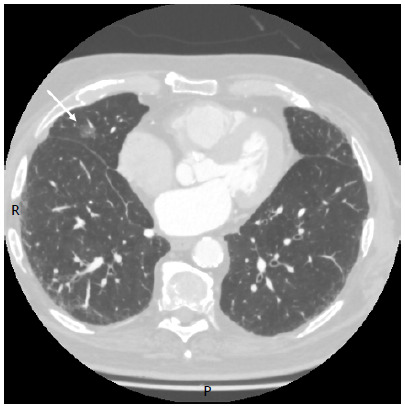

Indocyanine green used in association with a surgical hemostatic agent as a fiducial marker to reduce overflow during robot-assisted thoracic surgery.